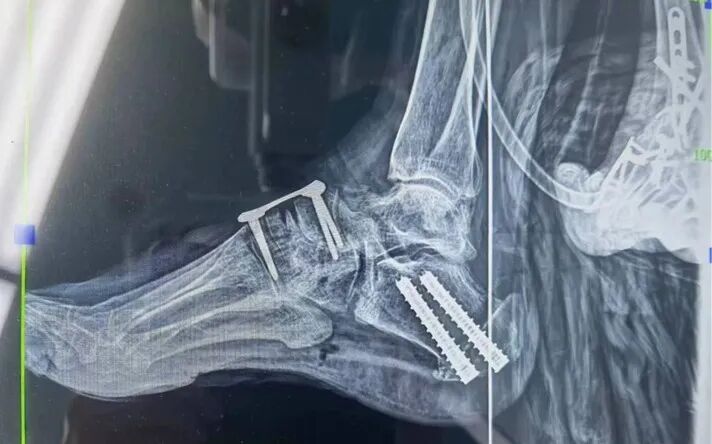

術(shù)后,患者疼痛逐漸減輕,術(shù)后7天疼痛癥狀完全消失,復(fù)查片子顯示左足內(nèi)翻糾正。目前,患者已康復(fù)出院,可以“腳踏實(shí)地”地開始嶄新的生活了。

術(shù)后足部

術(shù)后X光片顯示患者左足內(nèi)翻糾正